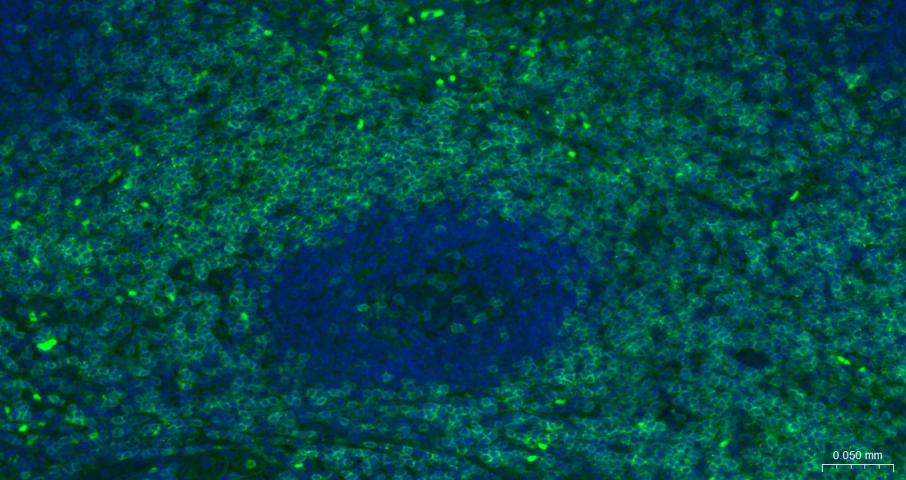

IFHuman, Mouse, Rat1:500-2000